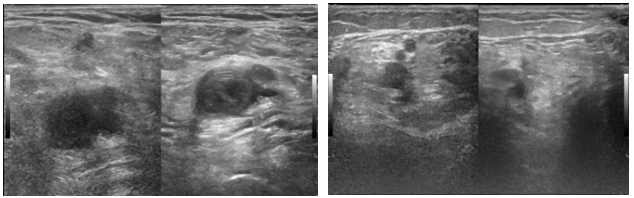

Hình 4: Huyết khối tĩnh mạch đùi – khoeo trái trên siêu âm

Bệnh nhân nữ, 65 tuổi, nhập viện vì phù cẳng chân trái. Bệnh nhân không ghi nhận tiền căn bệnh lý tim mạch trước đây. Cách nhập viện khoảng 3 tuần, bệnh nhân thấy đau cẳng chân trái tăng dần. Cách nhập viện khoảng 1 tuần, bệnh nhân thấy chân trái đau nhiều, hạn chế đi lại, kèm sưng phù chân trái nên nhập viện. Khám ghi nhận, sinh hiệu trong giới hạn bình thường, không sốt: mạch = 80 lần/phút, HA = 130/80 mmHG, nhiệt độ = 36,8oC, nhịp thở = 20 lần/phút, SpO2 = 98%/khí trời. Khám ghi nhận sưng phù chân trái, đường kính chân trái lớn hơn chân phải. Điện tâm đồ trong giới hạn bình thường. Siêu âm tĩnh mạch chi dưới ghi nhận: huyết khối không hoàn toàn giai đoạn cấp – bán cấp các tĩnh mạch sâu và tĩnh mạch nông đùi trái (tĩnh mạch đùi, tĩnh mạch khoeo, tĩnh mạch hiển bé) và huyết khối không hoàn toàn ở đoạn đầu tĩnh mạch chày sau và tĩnh mạch chày trước bên trái.